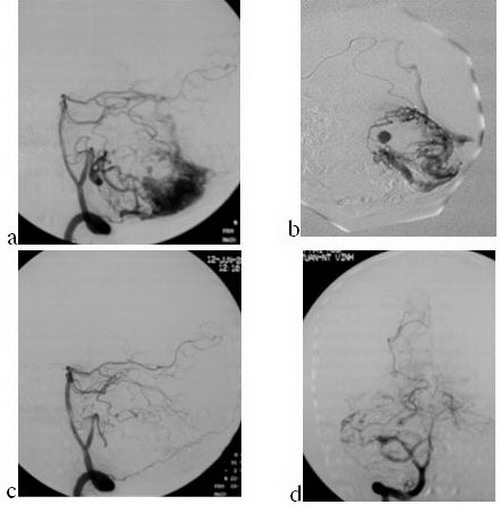

Trường hợp 2: tổn thương vùng tiểu não có giả phình mạch nuôi.

Hình 2:

Bệnh nhân nữ, 27 tuổi, đột ngột đau gáy và nôn; chụp CHT (04.06.07): xuất huyết

tiểu não; chụp mạch não (12.06.07): DDĐTM tiểu não phải, kích thước 2.5 x 4 cm,

tĩnh mạch dẫn lưu nông (Spetzler-Martin III) (a); ổ dị dạng 3 cuống nuôi: một

cuống nuôi từ ĐM tiểu não trên, 2 cuống từ ĐM tiểu não dưới trong đó một cuống

có giả phình xa (b); tiến hành gây tắc 3 cuống với thể tích lần lượt là 0.9 ml,

0.5 ml và 0.6ml (cuống có giả phình động mạch) với cùng tỷ lệ Histoacryl/

Lipiodol: 0.5ml/2.5ml. Chụp kiểm tra sau nút tắc hoàn toàn ổ dị dạng, không thấy

tĩnh mạch dẫn lưu thì sớm (c,d). Hiện bệnh nhân không có biểu hiện dấu hiệu

thần kinh sau nút.

Hình 2:

Bệnh nhân nữ, 27 tuổi, đột ngột đau gáy và nôn; chụp CHT (04.06.07): xuất huyết

tiểu não; chụp mạch não (12.06.07): DDĐTM tiểu não phải, kích thước 2.5 x 4 cm,

tĩnh mạch dẫn lưu nông (Spetzler-Martin III) (a); ổ dị dạng 3 cuống nuôi: một

cuống nuôi từ ĐM tiểu não trên, 2 cuống từ ĐM tiểu não dưới trong đó một cuống

có giả phình xa (b); tiến hành gây tắc 3 cuống với thể tích lần lượt là 0.9 ml,

0.5 ml và 0.6ml (cuống có giả phình động mạch) với cùng tỷ lệ Histoacryl/

Lipiodol: 0.5ml/2.5ml. Chụp kiểm tra sau nút tắc hoàn toàn ổ dị dạng, không thấy

tĩnh mạch dẫn lưu thì sớm (c,d). Hiện bệnh nhân không có biểu hiện dấu hiệu

thần kinh sau nút.